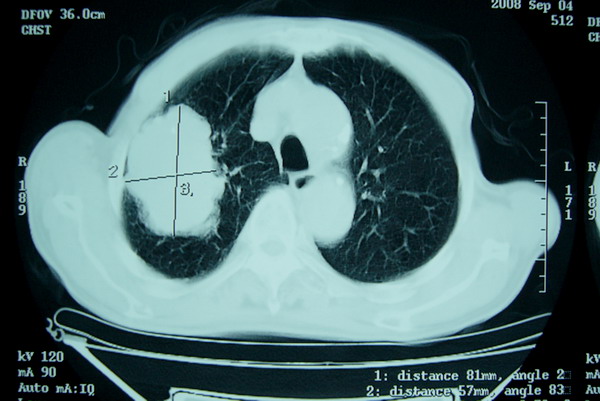

标题: CT15579:男 86岁 咳嗽 咳少量白痰 发热2天 吸烟史60年 [打印本页]

标题: CT15579:男 86岁 咳嗽 咳少量白痰 发热2天 吸烟史60年

分叶及少量边缘性钙化,老年人,周围性肺癌首先考虑。

右肺上叶巨大软组织肿块,轮廓不规则,纵隔内有肿大淋巴结,首先考虑肺癌。

右上肺一不规则团块,边缘有分叶和毛刺,纵隔有淋巴结肿大。右肺周围性肺癌首先考虑。